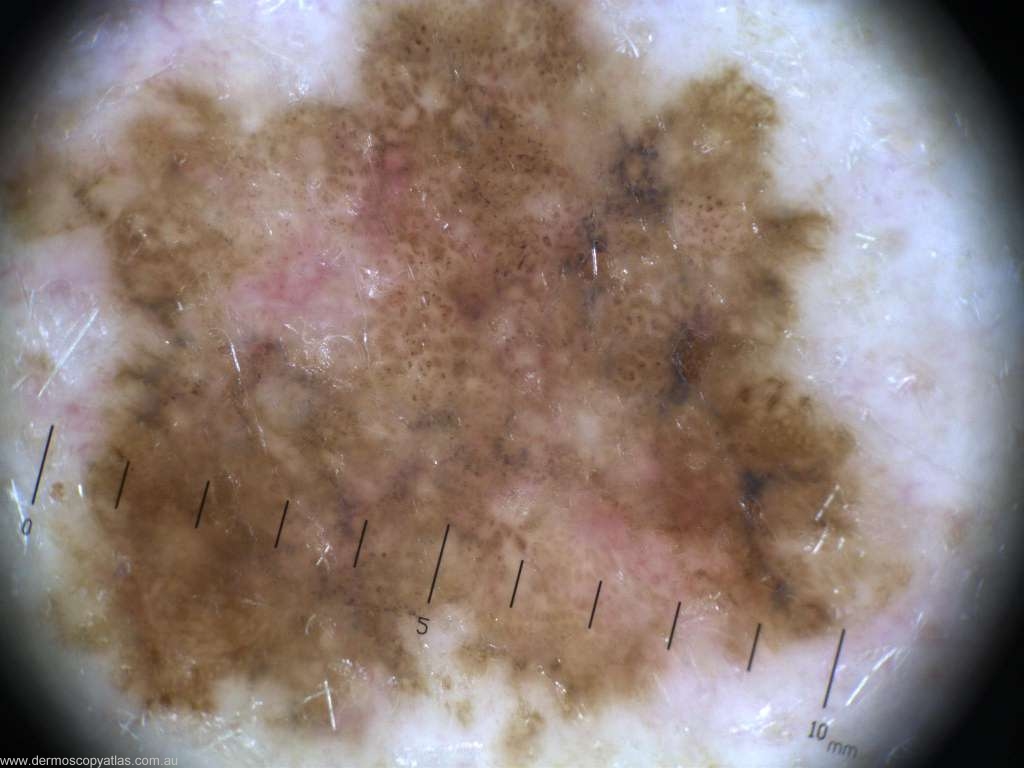

Case 6 47 year old male. Routine check. No history. R upper arm.

Question: Which diagnosis is correct? Consider Melanoma in situ, Seborrhoeic keratosis, Melanoma invasive, Junctional nevus, Pigmented BCC, Dysplastic nevus, LPLK and Pigmented IEC